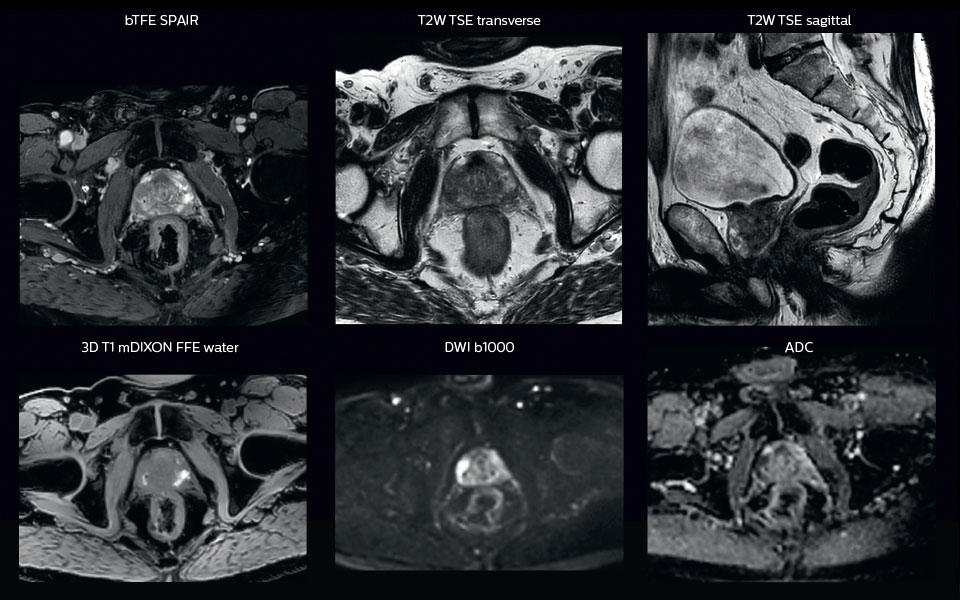

“All our patients undergo an MRI exam – along with CT – before radiotherapy of the prostate,” says Dr. Philippens. “For prostate delineation, we are scanning a balanced TFE with fat suppression. We can also see the gold fiducial markers in these images, which are used for position verification and are therefore used for registration to CT. For geometric accuracy of the image, we choose a 3D sequence, which is corrected for the gradient non-linearities in all directions.

“In addition to helping in delineation of the prostate, MRI also helps in visualizing the lesions inside the prostate, which may not be possible in CT.

“When we can visualize intraprostatic lesions, the radiation therapist can then plan to boost them, giving a higher dose to those lesions instead of giving a uniform dose to the whole prostate, in the hope to better treat the patient and have less risk of recurrent tumors. However, this is not yet clinical routine. For visualizing the lesions, we not only use anatomical, T2-weighted imaging, but also diffusion weighted MRI and dynamic contrast- enhanced MRI."

A 63-year-old patient with prostate cancer, cT3bNxM, Gleason 7, underwent MRI on Ingenia 3.0T MR-RT before radiation therapy.

Intraprostatic lesions are visible on the bTFE MR image, but not on the CT image. MRI shows excellent soft-tissue contrast for the visualization of critical structures like the rectum and penile bulb.